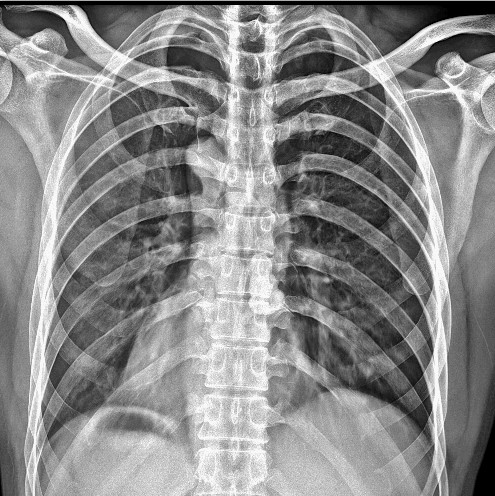

X射线在医学诊断中被广泛应用,其主要原理包括穿透作用、差别吸收、感光作用和荧光作用。当X射线穿过人体时,其会被不同程度地吸收,比如说骨骼吸收的X射线量会比肌肉吸收的量多。这样,在穿过人体后,X射线的强度就会因部位密度的不同而不同,使得在荧光屏或摄影胶片上的荧光或感光效应也不同。于是,在荧光屏或摄影胶片上显示的阴影密度就能反映出人体该部位的情况。结合临床表现、化验结果和病理诊断,医生就能判断出该部位是否正常。因此,X射线诊断技术 直是世界上早应用的非侵入性内脏检查技术。